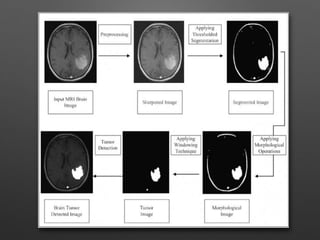

From the obtained images the one responsible for

tumor is choosen.

That image is subtracted from the original gray

scale image to get the tumor detected image.

METHODOLOGY • Four Stages: A.Pre-Processing C. Segmentation D.Feature Extraction B. Skull Stripping

From the obtainedimages the one responsible for tumor is choosen. That image is subtracted from the original gray scale image to get the tumor detected image.